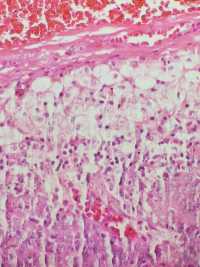

求助老师们,肘部内侧肿物

性别

女

年龄

49

肘部内侧肿物8年,压痛,界清,可活动

肘部内侧肿物

椭圆形灰粉淡黄组织一块,2.3×1.4×1.2cm,包膜完整,切面灰粉黑褐色,实性,质中

考虑: 滑模血管瘤?